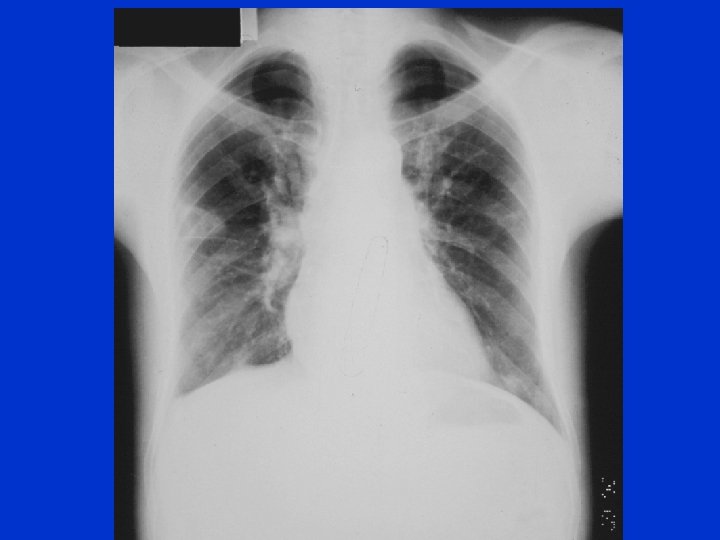

Caso Clínico (fevereiro/2012): Homem, 21 anos, branco, com edema há 1 semana atingindo anasarca. Fazia uso recreacional de cocaína e LSD e sexo sem proteção com mulheres com vida promíscua. Ex físico: edema 3+ em membros inferiores atingindo até 1/3 distal das coxas. PA: 130 x 70 mm. Hg; FC= 80 bpm; presença de gânglios palpáveis inguinais e submandibulares, bilateralmente, medindo até 1, 5 cm, não dolorosos. Urina rotina: proteínas +++; leucócitos: ; hemácias: 6/campo, cilindros hialinos; proteinúria: 4100 mg/24; Albumina sérica: 0, 9 g/d. L; proteínas totais: 4, 2 g/d. L; Creatinina: 1, 0 mg/d. L; Colesterol total 233; LDL: 166; C 3: 188; C 4: 36; Hb: 16, 8 g%; GB: 10200; Plaquetas: 183. 000/mm 3

Biópsia renal: Nefropatia membranosa VDRL: reagente 1/64; Reação de hemaglutinação para sífilis: positiva FAN, ANCA, virus B, vírus C, HIV negativos Tomografia evidenciou gânglios peritoneais e pulmonares. Tratamento: üPenicilina benzatina, 2. 400. 000 UI, via intramuscular/semana, por 3 doses. Após 6 semanas: üProteinúria de 246 mg/24 h üAlbumina 3, 8; Creatinina: 0, 8 üGânglios não palpáveis e sem edema.